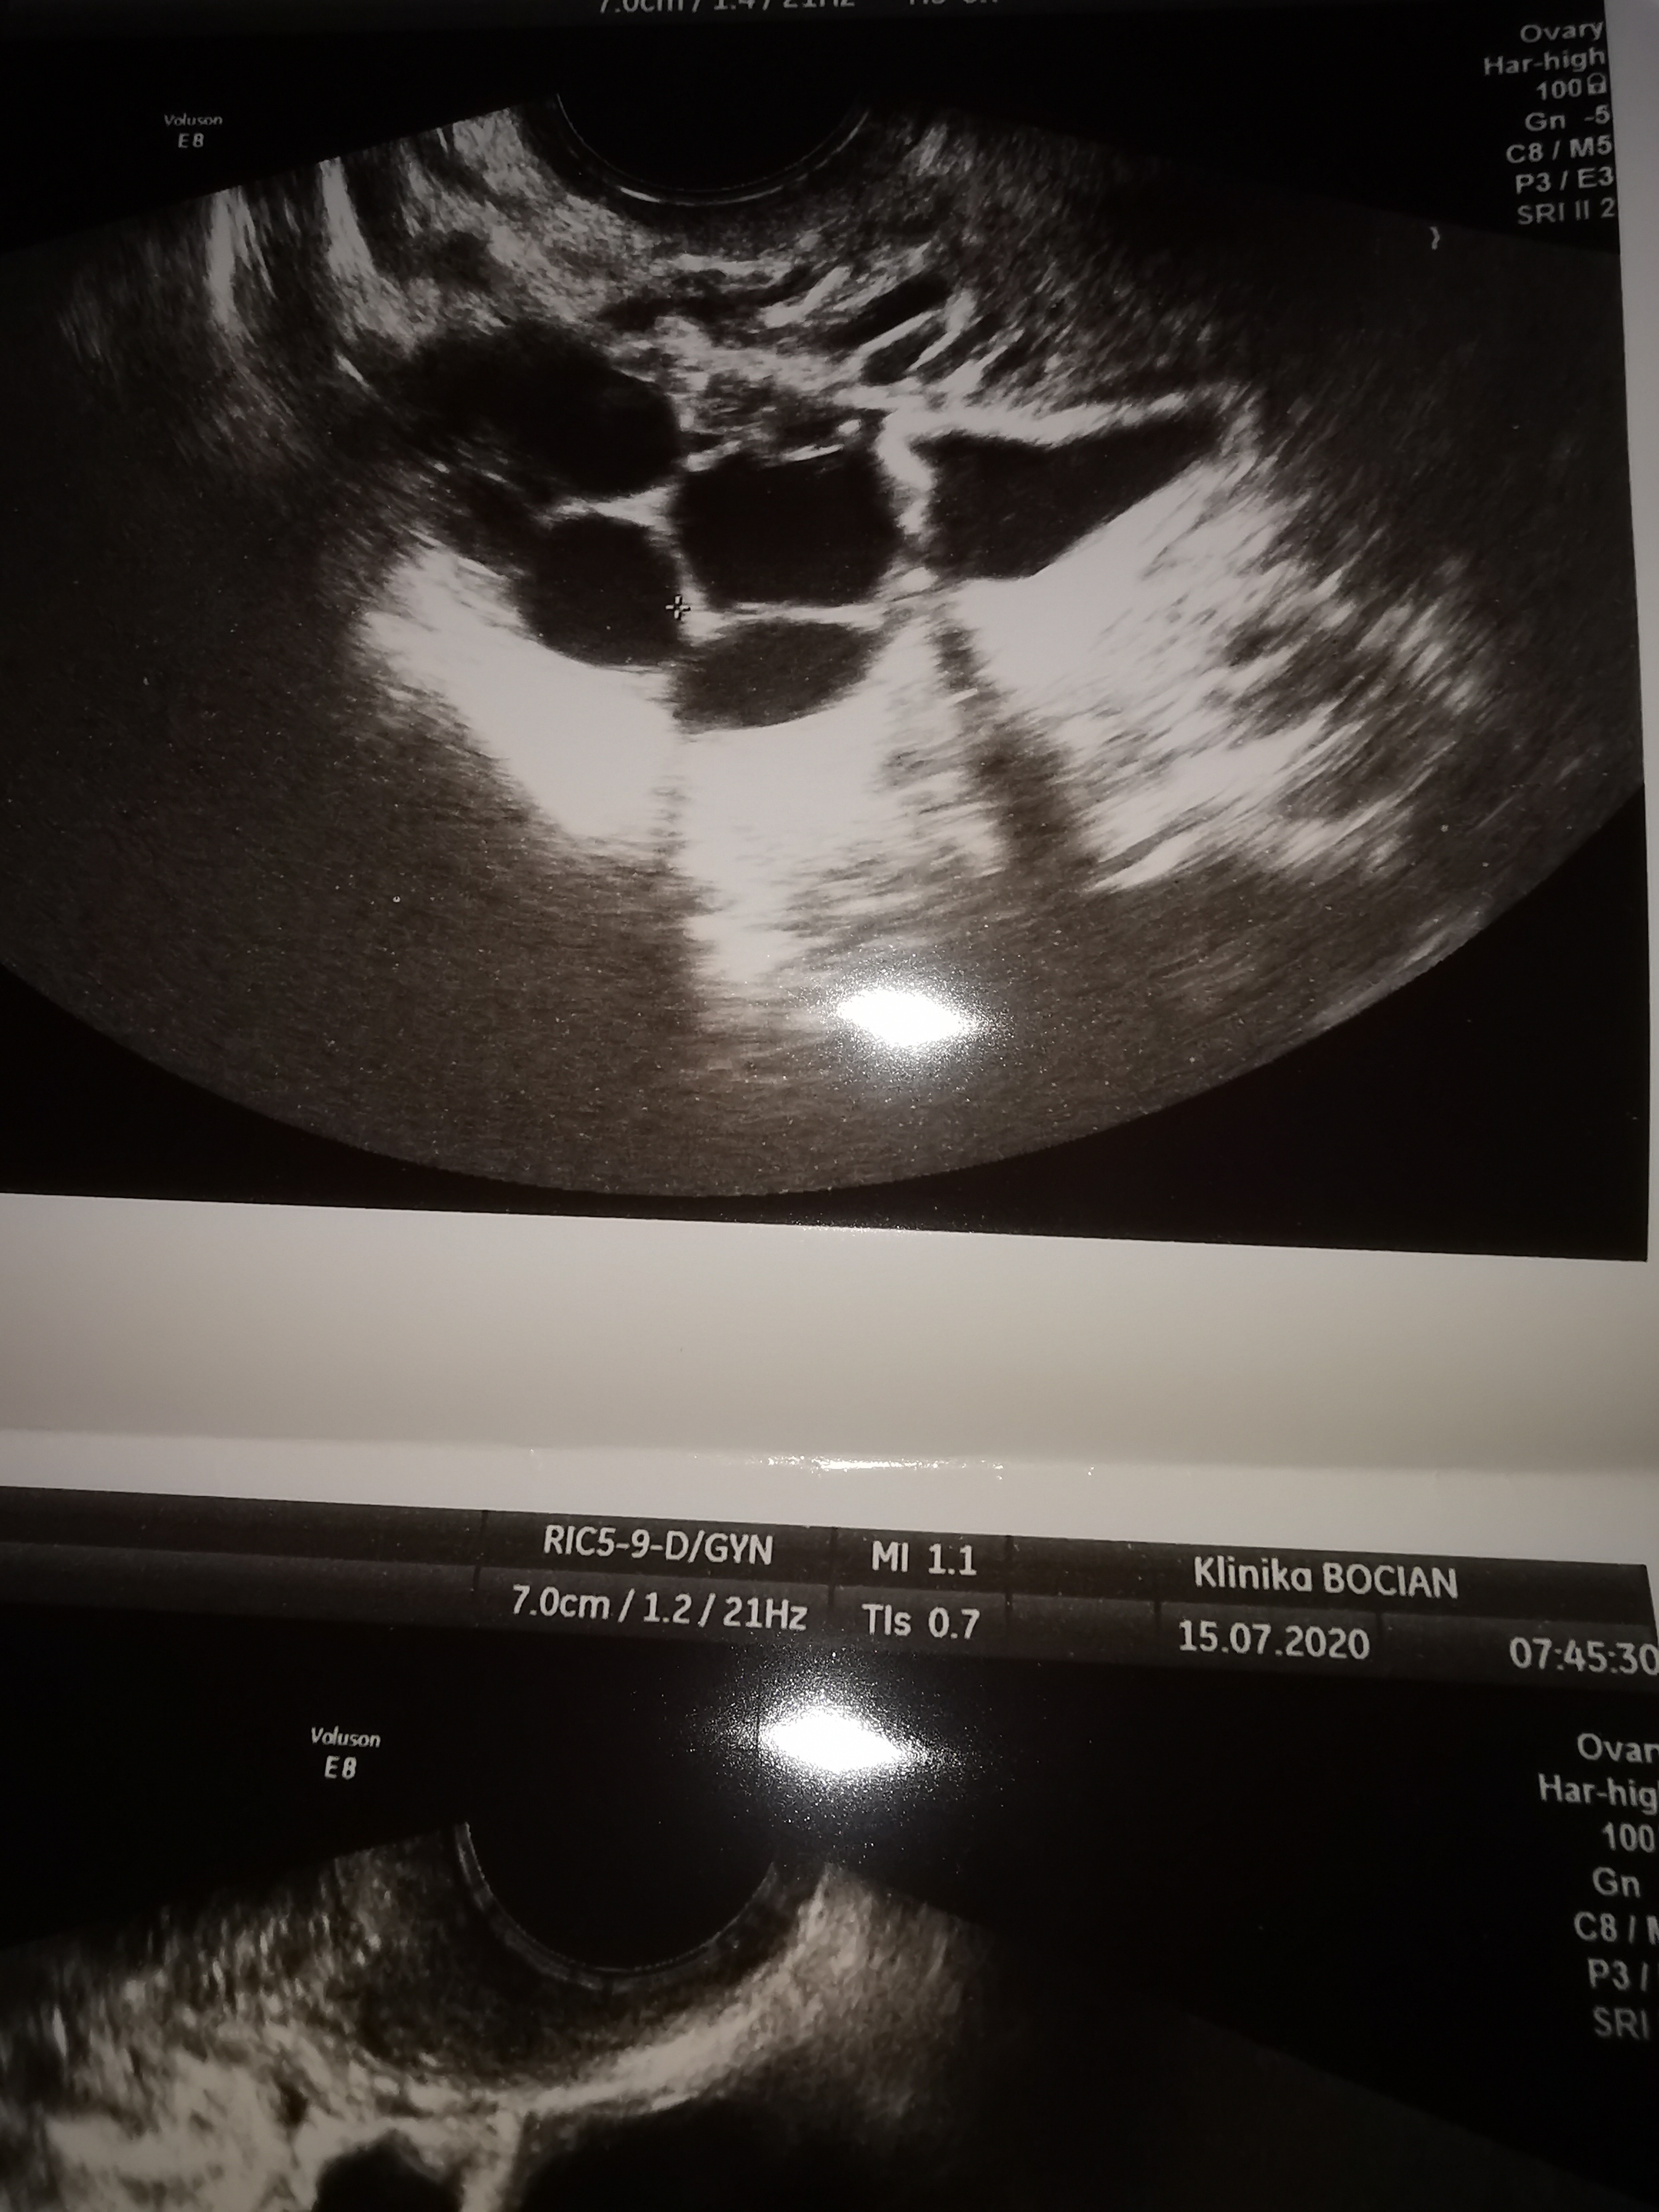

Moje jajniki wyglądają tak jak na zdjęciu... Jakbym była po stymulacji, tylko że ja stymulacji nie przechodziłam od 2018... Lekarz za każdym razem coś tam gadał, że to dziwne, ale w końcu kazał wstępnie zrobić marker nowotworowy CA125... właśnie odebrałam wynik... Norma przekroczona 2 razy....

Aż nie wiem co mam zrobić...

• IMG_20200716_094729.jpg

1,9 MB · Wyświetleń: 129